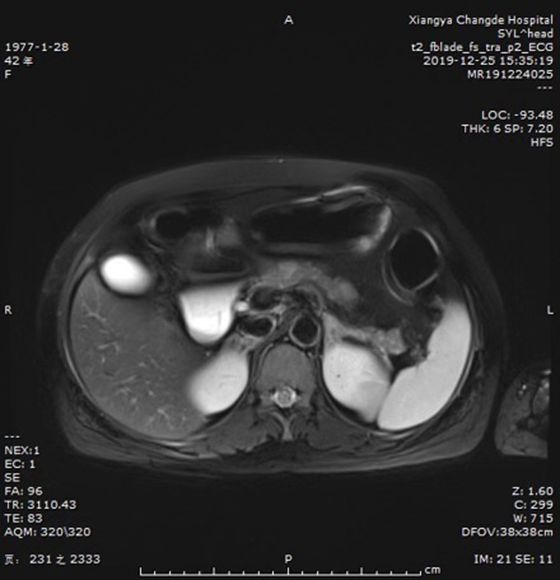

近日,湘雅常德医院普外科再次成功为一名中年女士切除一重达5.5斤的腹膜后肿瘤,目前患者恢复良好,择日出院。据悉,这是近2个月以来我院接诊的第4例巨大腹膜后肿瘤患者,其中最重1例近10斤。  ...

黄女士9年前患上了严重“低血糖”,9年间去往各大医院内分泌科寻求治疗,均未取得明显疗效。今年42岁的她由于长期低血糖,出现记忆力下降,甚至偶有意识丧失的症状,病情逐渐加剧,“病根”却未得到控制。 ...